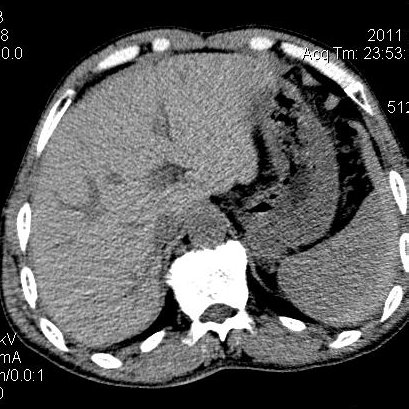

肝左叶发育异常

男性,55岁,骑摩托车摔倒后入院,自述右上腹疼痛

[backcolor=#FF0000]第一次诊断的时候也是这么肯定,可是床旁超声检查并没有发现明显异常,而且患者的一般症状都良好。还好临床只是保守治疗,没有立即手术,第二次复查的时候没有一点变化,又做了MRI检查,没有血肿,

这是一例肝左叶发育异常的,很个性吧~[/backcolor]